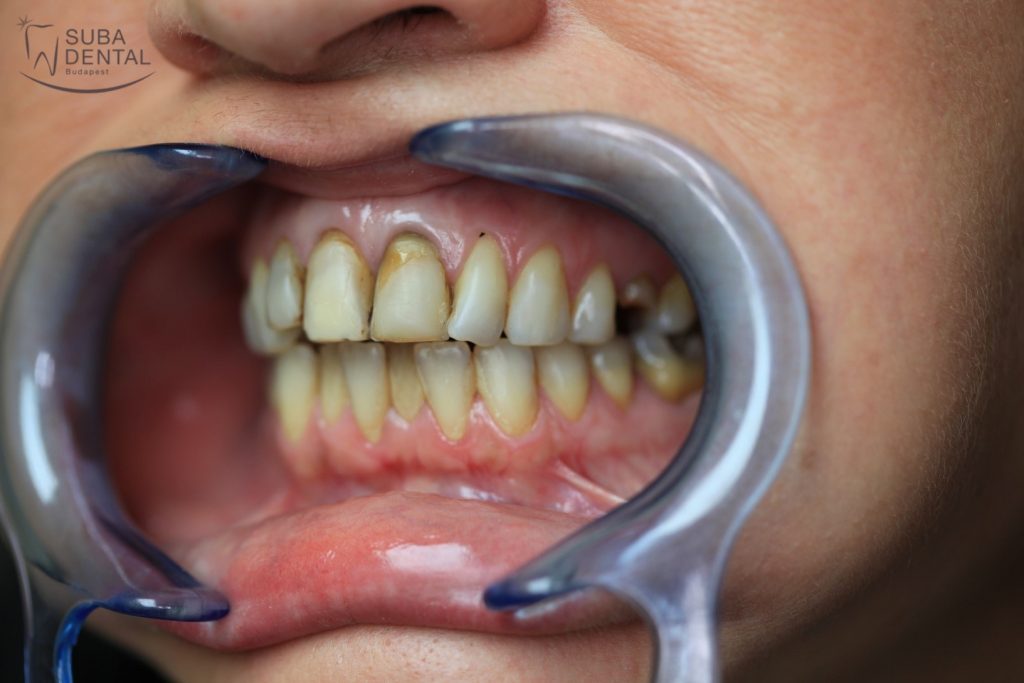

Our female patient, aged 37, reported to our clinic with the following problems:

- She had become rather reclusive on account of her teeth.

- Restoration of aesthetics was a top priority so she could feel at ease to smile again.

- She sought to have teeth of uniform colour and shape.

At the first encounter a panoramic radiograph and a series of photographs were taken of the teeth. The radiograph and the clinical examination of the mouth revealed that the upper left second premolar had chipped off, had to be root canal treated again and reinforced with a post-and-core abutment so that a crown could be securely mounted on it. The upper central incisors and the right lateral incisor had been root canal treated and had to be reinforced with a post-and-core abutment as well. The options were discussed with the patient and our choice fell on zirconia crowns for the upper incisors and the chipped-off premolar. Aesthetics can best be restored with metal-free E.Max crowns but since the teeth were root canal treated and had post-and-core abutments we opted for zirconia crowns rather than all-ceramic ones.

Before